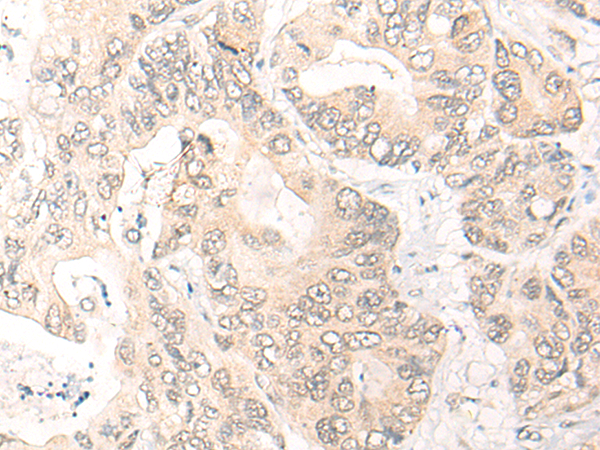

IHC positive control: |

Human gastric cancer; Human ovarian cancer |